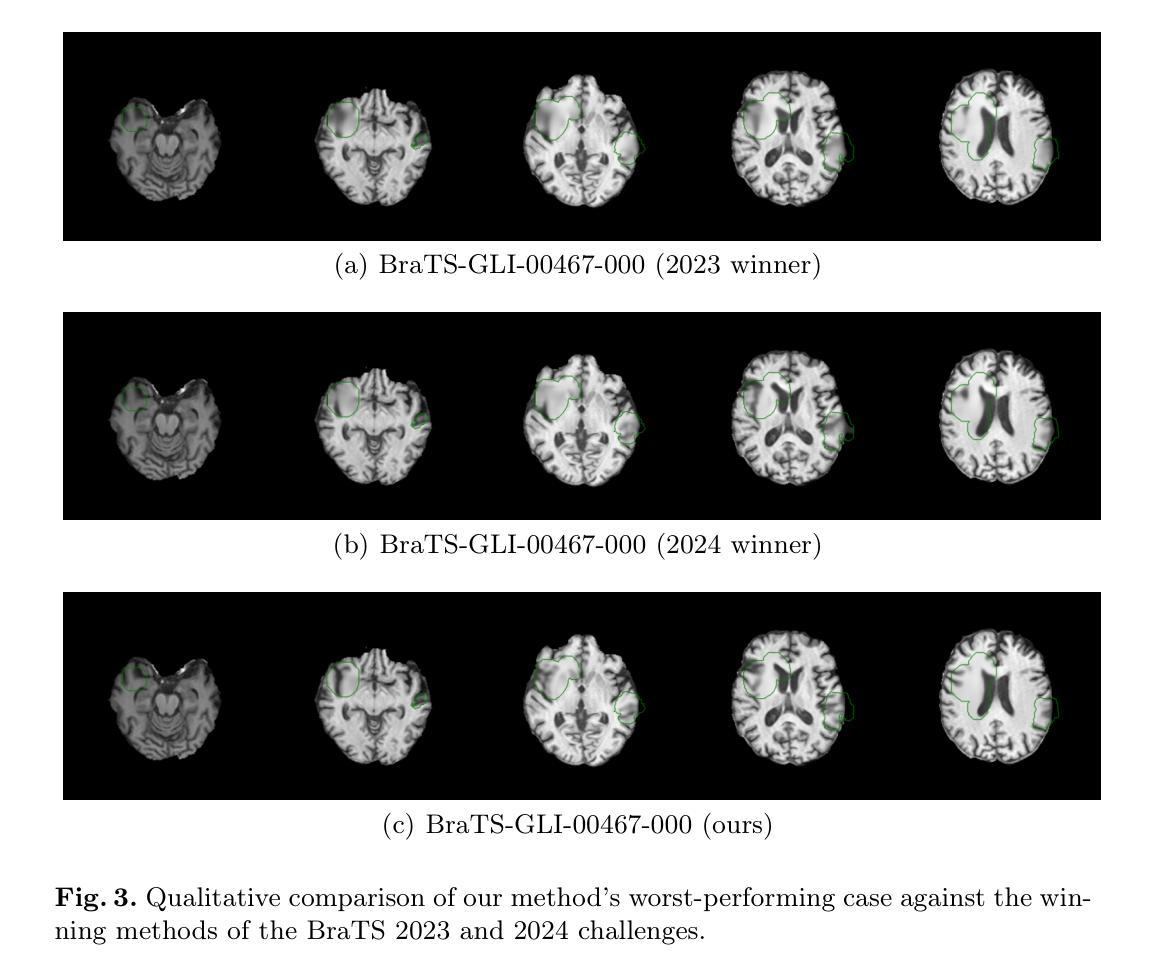

The ASNR-MICCAI BraTS-Inpainting Challenge was established to mitigate dataset biases that limit deep learning models in the quantitative analysis of brain tumor MRI. This paper details our submission to the 2025 challenge, a novel deep learning framework for synthesizing healthy tissue in 3D scans. The core of our method is a U-Net architecture trained to inpaint synthetically corrupted regions, enhanced with a random masking augmentation strategy to improve generalization. Quantitative evaluation confirmed the efficacy of our approach, yielding an SSIM of 0.873$\pm$0.004, a PSNR of 24.996$\pm$4.694, and an MSE of 0.005$\pm$0.087 on the validation set. On the final online test set, our method achieved an SSIM of 0.919$\pm$0.088, a PSNR of 26.932$\pm$5.057, and an RMSE of 0.052$\pm$0.026. This performance secured first place in the BraTS-Inpainting 2025 challenge and surpassed the winning solutions from the 2023 and 2024 competitions on the official leaderboard.

ASNR-MICCAI BraTS-Inpainting挑战赛旨在减轻数据集偏见,这些偏见限制了深度学习模型在脑部肿瘤MRI定量分析中的应用。这篇论文详细描述了我们对2025年挑战赛的提交内容,即一种用于在3D扫描中合成健康组织的新型深度学习框架。我们的方法的核心是U-Net架构,该架构经过训练可用于填充合成损坏区域,并采用随机掩膜增强策略来提高泛化能力。定量评估证实了我们方法的有效性,在验证集上,结构相似性指标(SSIM)为0.873±0.004,峰值信噪比(PSNR)为24.996±4.694,均方误差(MSE)为0.005±0.087。在最后的在线测试集上,我们的方法实现了SSIM 0.919±0.088,PSNR 26.932±5.057和均方根误差RMSE 0.052±0.026。这一表现使我们在BraTS-Inpainting 2025挑战赛中获得了第一名,并在官方排行榜上超越了2023年和2024年的获胜解决方案。

Summary

本论文提交了一项针对ASNR-MICCAI BraTS-Inpainting挑战的新型深度学习框架,旨在合成健康组织在三维扫描中的修复技术。通过训练U-Net架构来填充合成破坏区域,并使用随机掩膜增强策略提高泛化能力。定量评估证实此方法有效,在验证集和最终测试集上均取得优异成绩,获得BraTS-Inpainting 2025挑战第一名。

Key Takeaways

1. ASNR-MICCAI BraTS-Inpainting挑战旨在解决深度学习模型在脑肿瘤MRI定量分析中的数据集偏见问题。

2. 论文提出了一种新型的深度学习框架,用于合成三维扫描中的健康组织修复技术。

3. 该方法的核心是训练的U-Net架构,用于填充合成破坏区域。

4. 使用随机掩膜增强策略提高了模型的泛化能力。

5. 定量评估表明,该方法在验证集上取得了优异的性能指标,包括SSIM、PSNR和MSE。

6. 在最终测试集上,该方法性能卓越,获得BraTS-Inpainting 2025挑战第一名。